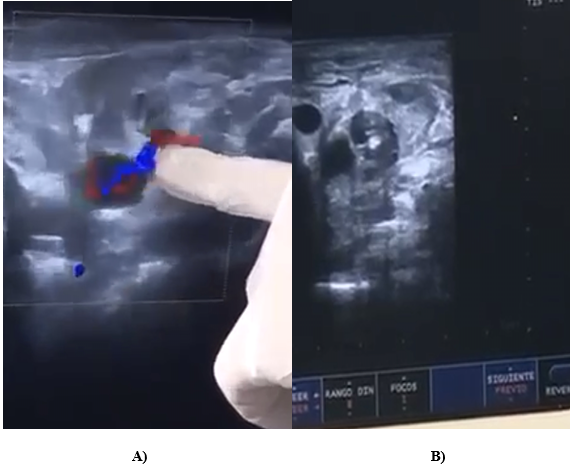

Therefore, treatment was performed with fibrin adhesive injection in carotid pseudoaneurysm, with a size of 20mm X 15mm, neck of 2.5 mm. Fibrin adhesive solution of 3 ml-1500 IU was used, using 1.5ml-750 IU, with 21 G needle (according to technique), under local anesthesia,9 noting the complete closure through echo-Doppler control (Figure 2) and good tolerance of the procedure.

Figure 2 Occluded pseudoaneurysm.

Simultaneously, a transcranial echocardiography control was performed, which did not show any change. After 3 days, a control with Doppler ultrasound was performed, which showed no flow, and clinically no neurological signs.